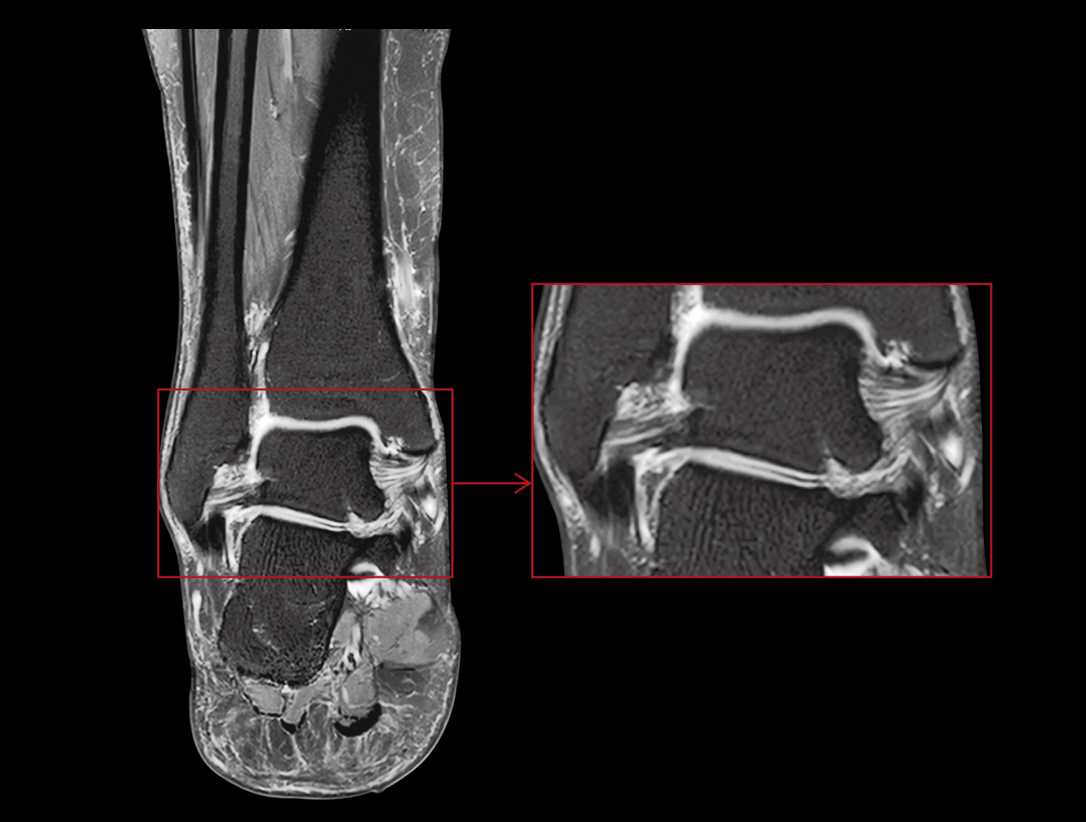

32/48 고밀도 RF 채널은 통합 고밀도 코일과 함께 사용되어 이미지의 신호 대 잡음 비율(SNR)을 크게 향상시킵니다.